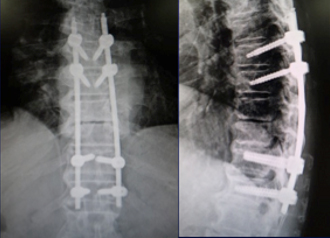

(左)第12胸椎および第1腰椎の骨粗鬆症性椎体骨折を認めます。(中)MRIでは第1腰椎に大きな骨欠損を認め、骨折が難治性で不安定であることを示しています。(右)第1腰椎に椎体形成術を施行し、さらに骨が脆かったため、頭尾側にスクリューを挿入して固定しています。